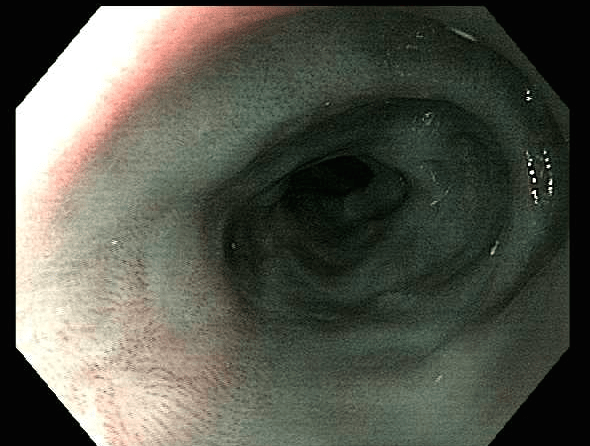

Three-month follow up exam - ESD scar and healingThree-month follow up exam – ESD scar and healing

The endoscopy performed at the three-month follow up showed the lesion to be well healed. PET-CT imaging found no evidence of recurrence at six months.

The patient will undergo surveillance endoscopy every three months for the first year and then yearly exams thereafter. Similar outcomes for patients with early cancers associated with Barrett’s esophagus have also been achieved.